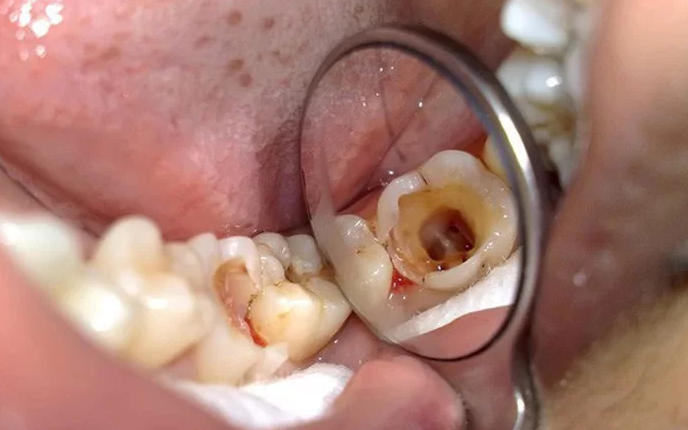

Răng hàm bị sâu là tình trạng thường gặp ở cả trẻ em và người lớn. Việc này không chỉ khiến cho vấn đề nhai, nuốt thức ăn trở nên khó khăn mà còn ảnh hưởng đến yếu tố thẩm mỹ. Thậm chí sâu răng còn gây ra biến chứng nguy hiểm cho người bệnh.

Răng hàm gồm các răng số 6, răng số 7 và răng số 8. Do răng hàm nằm ở vị trí trong cùng của cung hàm nên ta thường khó quan sát và vệ sinh sạch sẽ, dẫn đến rất dễ tạo mảng bám trên răng và tạo điều kiện sinh sôi vi khuẩn, gây sâu răng. Khi răng hàm bị sâu, nha sĩ có thể chỉ định nhổ răng. Vậy quy trình nhổ răng hàm như thế nào?

Do giữ chức năng nhai chính trong cung hàm nên răng hàm thường xuyên phải tiếp xúc với thức ăn, thực phẩm có đường. Nếu không vệ sinh răng miệng đúng cách sẽ tạo điều kiện cho các vi khuẩn có cơ hội phát triển, tấn công men răng. Lâu dần, răng hàm sẽ dần chuyển sang màu đen, phá hủy men răng và ngà răng.